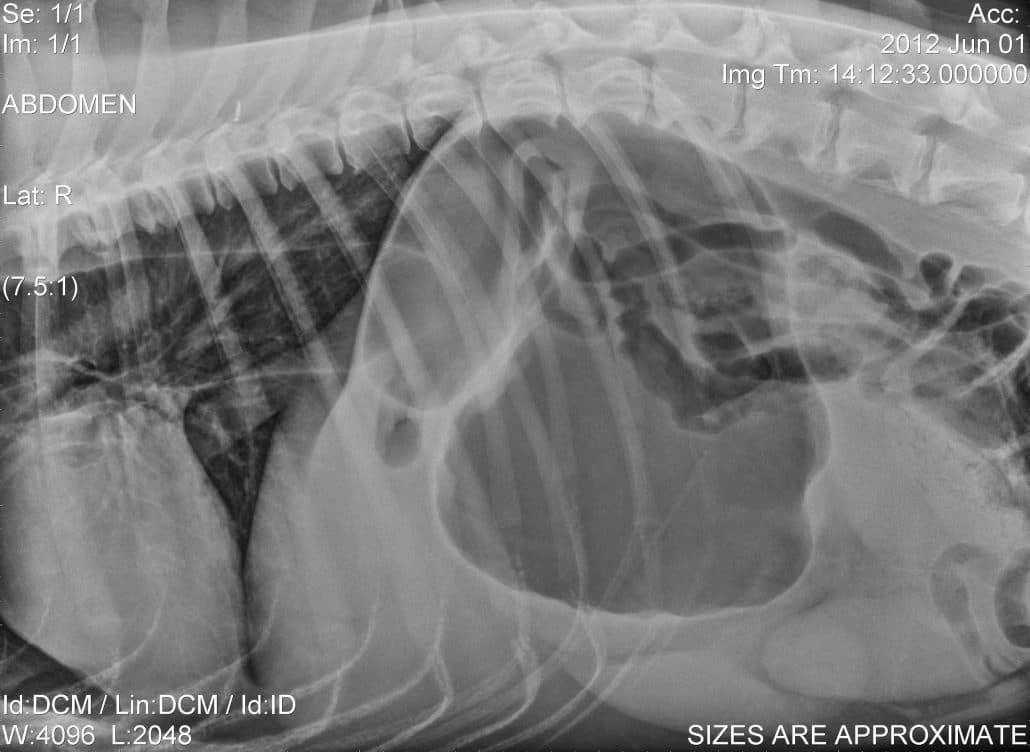

Gastric Dilation Volvulus (GDV)

The GDV is a life threatening condition that occurs in, usually, in older, larger breed dogs. The condition is commonly referred to as ‘bloat’ because the stomach becomes distended with gas. Dogs with GDV will typically present retching, depressed, have a distended appearing abdomen and may or may not be in cardiovascular shock. The condition tends to progress rapidly and if left untreated, will result in the patient’s death. A ‘bloat’ is always an emergency.